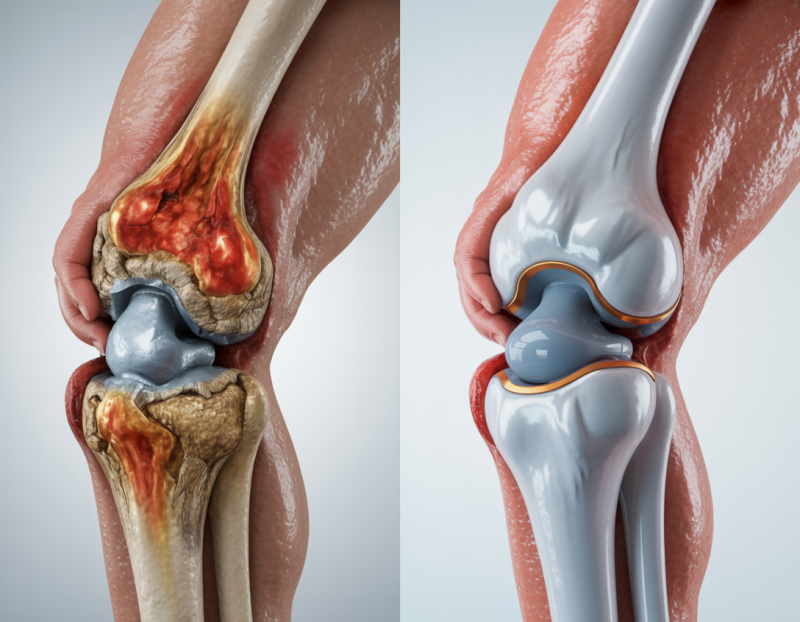

Problems We Treat

Dr. T. Sringari is one of Gurgaon's most experienced orthopedic surgeons, with over 15 years of surgical expertise in joint replacement, sports injuries, and arthroscopic procedures. He has performed over 1,500 joint replacements — including total knee, total hip, uni-compartmental, and revision joint replacements — and over 5,000 arthroscopic surgeries, making him one of the most hands-on orthopedic specialists in the region. Beyond the clinic, Dr. Sringari has published and presented 16 research papers at international conferences across the UK, Australia, Spain, and Turkey, and has provided medical care at major sports events including the ICL. Patients choose him not just for his surgical precision, but for the personalised recovery plans he builds for each individual.

I was suffering from severe knee pain for years. After my knee replacement at Polaris Hospital, I can walk freely again. The doctors & staff were extremely supportive for recovery.